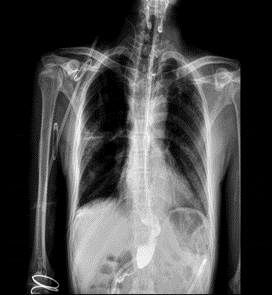

患者情況 + + + + 患者楊先生,57歲,既往肺結(jié)核病史,因2+月前因“吞咽困難”未予重視,出現(xiàn)進(jìn)食后嘔吐,嘔吐物為胃內(nèi)容物,近3月來體重下降約“10kg”,就診于外院,胃鏡提示食管占位鱗狀上皮重度異性增生,于2024年7月29日以“食管占位”收入我科繼續(xù)治療,頸部增強(qiáng)

CT提示食管下段鱗癌。結(jié)合患者既往肺結(jié)核病史肺功能及身體情況差。 術(shù)前相關(guān)影像學(xué)檢查 術(shù)前詳細(xì)討論,做好充分準(zhǔn)備 + + + + 術(shù)前,徐靜峰主任邀請(qǐng)麻醉科、腫瘤科、結(jié)核科以及輸血科等多個(gè)學(xué)科的專家進(jìn)行深入討論,一致決定為患者執(zhí)行一項(xiàng)頸胸腹三切口食管癌根治術(shù)。這是一次技術(shù)要求極高的四級(jí)手術(shù),術(shù)前準(zhǔn)備工作不僅包括精確的影像學(xué)和病理學(xué)評(píng)估,還必須應(yīng)對(duì)患者所面臨的多種基礎(chǔ)疾病和潛在并發(fā)癥的挑戰(zhàn)。 手術(shù)圓滿成功,彰顯團(tuán)隊(duì)實(shí)力 8月20日,徐靜峰主任團(tuán)隊(duì)在麻醉科和手術(shù)室的完美協(xié)作下,成功為楊先生在全身麻醉狀態(tài)下執(zhí)行了胸腹腔鏡聯(lián)合頸胸腹三切口食管癌根治術(shù)。手術(shù)過程中,麻醉順利進(jìn)行,手術(shù)也順利完成,術(shù)中出血量控制在約50毫升,達(dá)到了預(yù)期的理想效果。這次手術(shù)不僅彰顯了我院胸外科技術(shù)的進(jìn)一步提升,也展示了徐靜峰主任團(tuán)隊(duì)在食管癌治療領(lǐng)域的精湛技藝、細(xì)致護(hù)理,以及各科室之間卓越的協(xié)作能力。 術(shù)后精心護(hù)理,攻克疑難病癥 患者護(hù)理團(tuán)隊(duì)通過十二指腸營(yíng)養(yǎng)管為患者提供腸內(nèi)營(yíng)養(yǎng),注入流質(zhì)飲食。他們強(qiáng)化了對(duì)呼吸道、胃腸道、傷口及引流的管理,并進(jìn)行了細(xì)致的護(hù)理觀察。術(shù)后第二天,患者便能夠下床活動(dòng),到了第七天,患者已能正常經(jīng)口攝入流質(zhì)飲食。在二十天后,患者順利出院,期間未出現(xiàn)任何術(shù)后并發(fā)癥。這一過程表現(xiàn)出創(chuàng)傷小、風(fēng)險(xiǎn)低、出血少以及預(yù)后優(yōu)良的特點(diǎn)。 市公衛(wèi)中心胸外科團(tuán)隊(duì)將持續(xù)以患者為核心,提供卓越的醫(yī)療技術(shù)和一流的??谱o(hù)理服務(wù),攻克更多復(fù)雜病癥,為廣大的患者群體帶來新的希望。 胸外科小科普: ? 食管是將食物從口腔傳輸?shù)轿覆康墓艿馈?/p> 食管癌又叫食道癌好發(fā)于食管內(nèi)壁的上皮細(xì)胞,是作為世界常見的惡性腫瘤之一,全球約有40萬新發(fā)病例,約30萬人死于食管癌,中國(guó)是世界上食管癌發(fā)病率最高的地區(qū)之一,一般男性高于女性。 ? ? ? 發(fā)生食管癌的臨床表現(xiàn): 早期:1、梗咽感 2、胸骨后灼感 3、異物感 4、無癥狀; 進(jìn)展期:1、進(jìn)行性吞咽困難 2、嘔吐、3、后背疼痛 4、體重下降; 晚期:1、侵犯穿孔(疼痛、嗆咳、嘔血) 2、神經(jīng)受累(聲音嘶?。?3、消瘦、貧血、低蛋白 4、遠(yuǎn)處轉(zhuǎn)移。 什么情況會(huì)誘發(fā)食管癌:愛吃腌制食品、趁熱吃趁熱喝、煙酒不離手、遺傳因素。 在正常情況下,食管的耐受高溫在50-60,但對(duì)一般人來說,口腔覺得燙的時(shí)候,食物起碼是70左右了,超出了食管的承受能力。